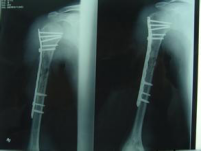

这是一种中和钢板的改版,针对于干部的粉碎骨折,通过透视下监视,使得钢板跨越骨折区域而固定骨折的近端和远端,骨折区域不进行固定。

该类技术主要是强调对位、对线、长度、旋转,中间粉碎可以不用处理,有效保护骨折断端血运,但是需要注意钢板需要有足够的长度,两端固定也需要有足够的螺钉数量。目前容易出现一些骨不连的现象,需要谨慎对待。